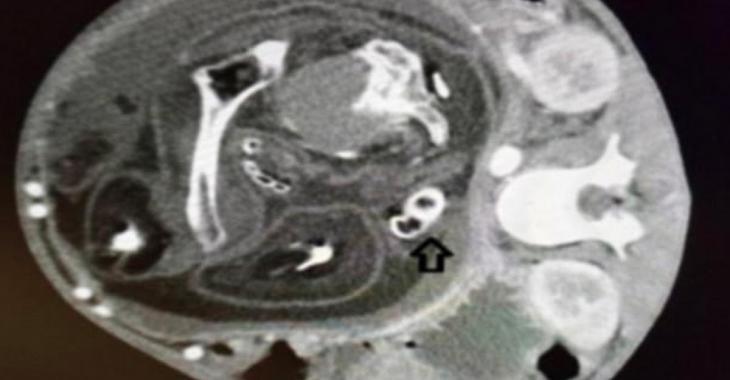

C'est donc en pratiquant des examens approfondis auprès du garçon que les médecins ont fini par découvrir que ce n'était pas une tumeur qui affectait la santé du garçon, mais bien le foetus de son frère jumeau qui était demeuré logé dans son ventre.

Le foetus était complètement recouvert de peau, il avait un pénis et de longs cheveux.

Les chirurgiens du Sultan Abdul Halim Hospital sont donc parvenus à retirer le foetus qui pesait un poids de 1.6 kg.

Évidemment, le foetus était non-viable, c'est-à-dire qu'il n'aurait pas pu vivre indépendamment. D'ailleurs, les médecins ont précisé qu'il n'avait pas de bouche, ni de placenta ou de cordon ombilical.

Ce n'est qu'en réalisant que la masse qui se logeait dans le ventre de l'adolescent comportait une colonne vertébrale que les médecins ont compris qu'il ne s'agissait pas d'une tumeur.

Par la suite, des analyses plus poussées ont démontré que la masse comprenait des morceaux de crâne humain, des os et même des vertèbres.